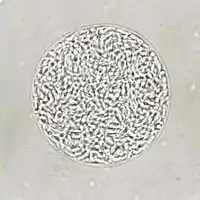

Cysts usually range in size between five and 50 µm in diameter,[36] (with 50 µm being about two-thirds the width of the average human hair).[37]